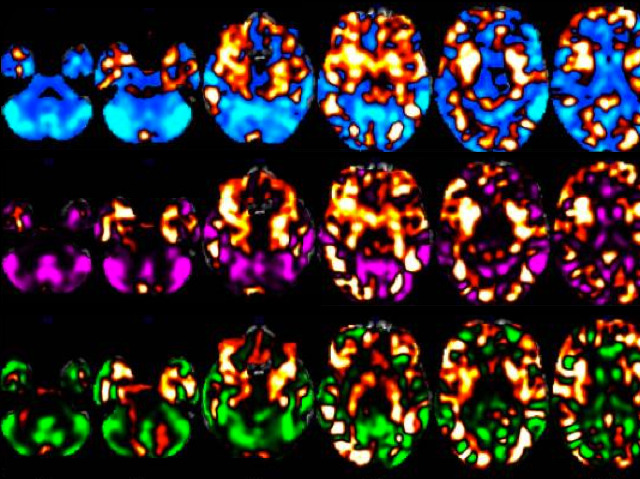

Is attention deficit hyperactivity disorder (ADHD) really a disorder or part of the normal range of human behaviour? One problem fuelling this controversy is the lack of a definitive diagnostic test. Currently ADHD is diagnosed by questionnaires, which since they rely on opinion are subjective. The resulting variation can lead to under- or over-diagnosing. Scientists have addressed this problem using magnetic resonance imaging combined with mathematical analysis to outline patterns in brain structure. The ADHD brain pattern (highlighted orange), is still clearly distinguishable when ‘overlaid’ on the ‘normal’ control pattern (blue and purple). Patients with autism (in green) were included as they share some symptoms with ADHD. This pattern recognition technique identified 79% of questionnaire-diagnosed ADHD patients and clearly distinguished ADHD from autism. It’s a promising first step towards an objective diagnostic test for ADHD.